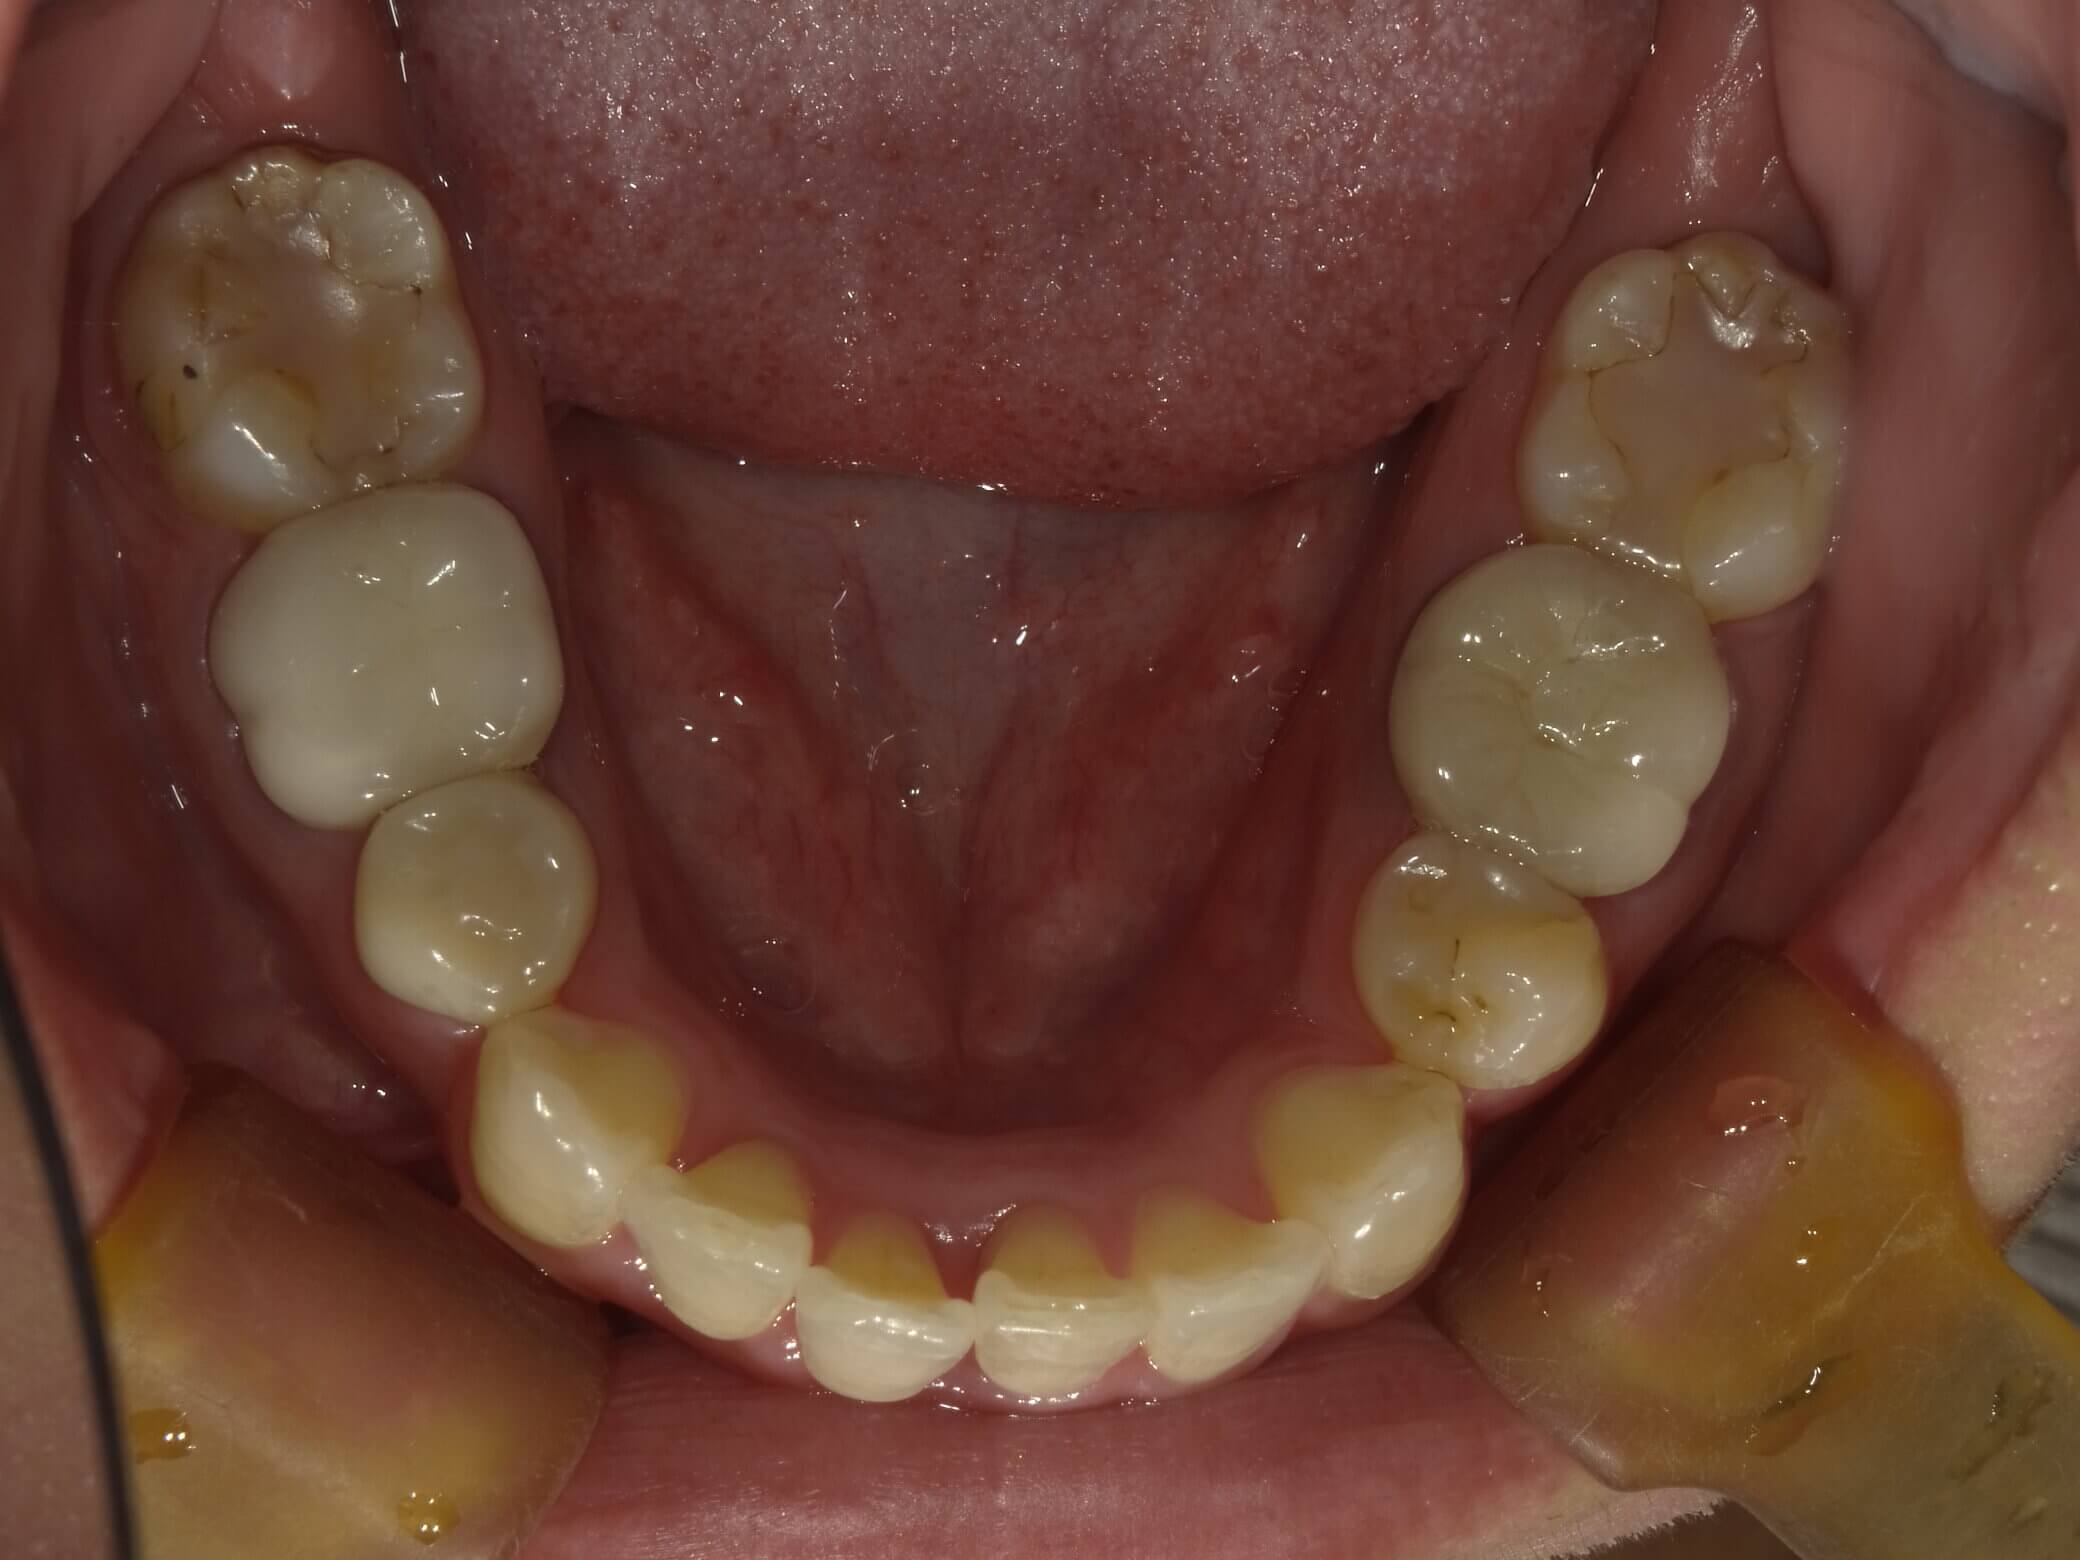

• 治療前

• 治療後